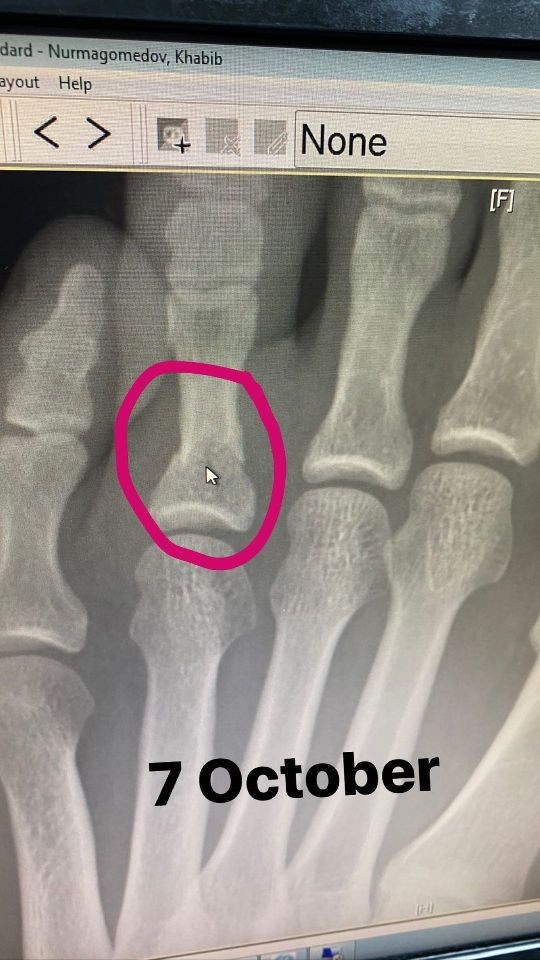

Sport.ru/ Бокс. Чемпион UFC в лёгком весе Хабиб Нурмагомедов добавил в "сториз" Instagram две фотографии. На снимках можно увидеть, какую травму боец получил в ходе подготовки к схватке с Джастином Гэтжи.

Первое фото, сделанное 7 октября, представляет собой рентгеновский снимок левой стопы. Второе фото, сделанное 8 октября, — обычный снимок того же участка.